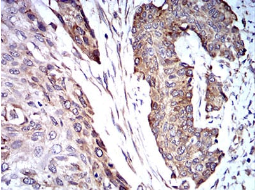

TRIM25 Mouse Monoclonal antibody[5B5B10]

IHC    1/200 - 1/1000